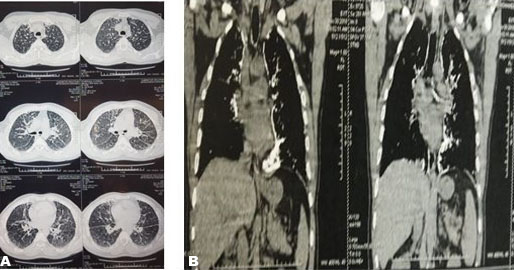

A 47-year-old male patient from a non-consanguineous family, who has never smoked, presented with complaints of persistent grade I dyspnea for the last six years, the physical examination was normal but later revealed wheezing groans, the chest X-ray revealed a bilaterally diffuse interstitial infiltrate (Figure 1), and the HRCT of the lungs showed diffuse, hyperdense micronodules throughout the whole lungs accompanied with bilateral calcific pleural thickening (Figure 2A and Figure 2B). Routine blood tests including serum phosphate and calcium were normal. The patient underwent bronchoscopy with broncho-alveolar lavage but did not demonstrate the characteristic microliths. Tuberculosis was ruled out due to the absence of acid-fast bacilli detection (Ziehl–Neelsen stain) in the lavage. Other differential diagnoses like asbestosis and hyperparathyroidism were ruled out.

Figure 2: Chest HRCT: hyperdense micronodules throughout the whole lungs accompanied with bilateral calcific pleural thickening.